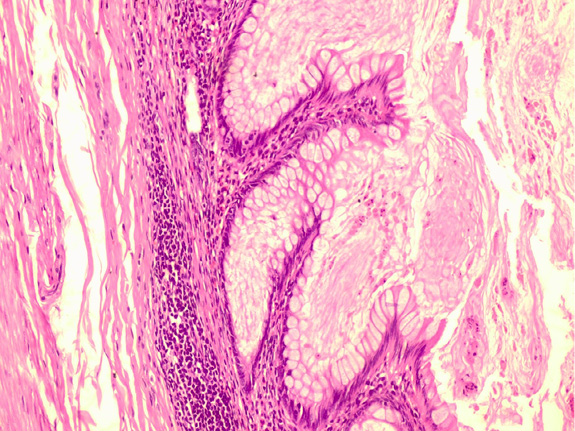

Pathologically, the appendix lumen diameter was 1.7 cm in the widest area. The appendix’s long axis was 7.5 cm. Mucoid material was observed in the lumen. The pathologic diagnosis was low-grade appendiceal mucinous neoplasm (appendiceal villous adenoma). Villiform mucinous epithelial proliferation was observed to replace the normal appendix mucosa [Figure 2]. It was observed that lymphoid tissue decreased In lamina propria and was replaced with fibrotic connective tissue [Figure 3]. Villiform mucinous epithelial proliferation appears to be composed of long mucinous epithelial cells with a low degree of nuclear atypia [Figure 4].

Figure 3. In the lamina propria, it is observed that lymphoid tissue decreases, instead, fibrotic connective tissue passes